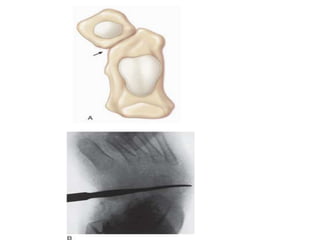

Radiology

• Plain radiograph: Can be assessed prior to

treatment with A-P & Lateral of foot

• Foot held in position of best correction, with weight-

bearing, or simulated weight-bearing

Anteroposterior view

• Talocalcaneal angle

• Calcaneal-second metatarsal angle

• Talus –first metatarsal angle

• Intermetatarsal angle